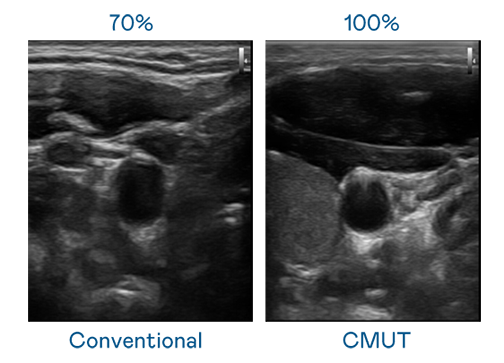

CMUT 技術是一種用電容式微機電元件來產生超音波訊號的技術。與傳統 PZT 壓電式技術相比,CMUT 頻寬增加 30%,更寬頻的超音波訊號讓影像解析度大幅提升,是實現高影像品質醫療超音波掃描、促進精準醫療發展的關鍵技術。

大頻寬帶來超清晰影像

超音波影像的解析度高低,首先取決於探頭能發出的訊號頻寬。永利娱乐城 CMUT 可提供高清晰的超音波訊號,提供高頻寬、高靈敏度、影像紋理細節更高的超音波影像,協助醫護人員縮短影像判讀時間及利用精準的醫療影像進行診斷。